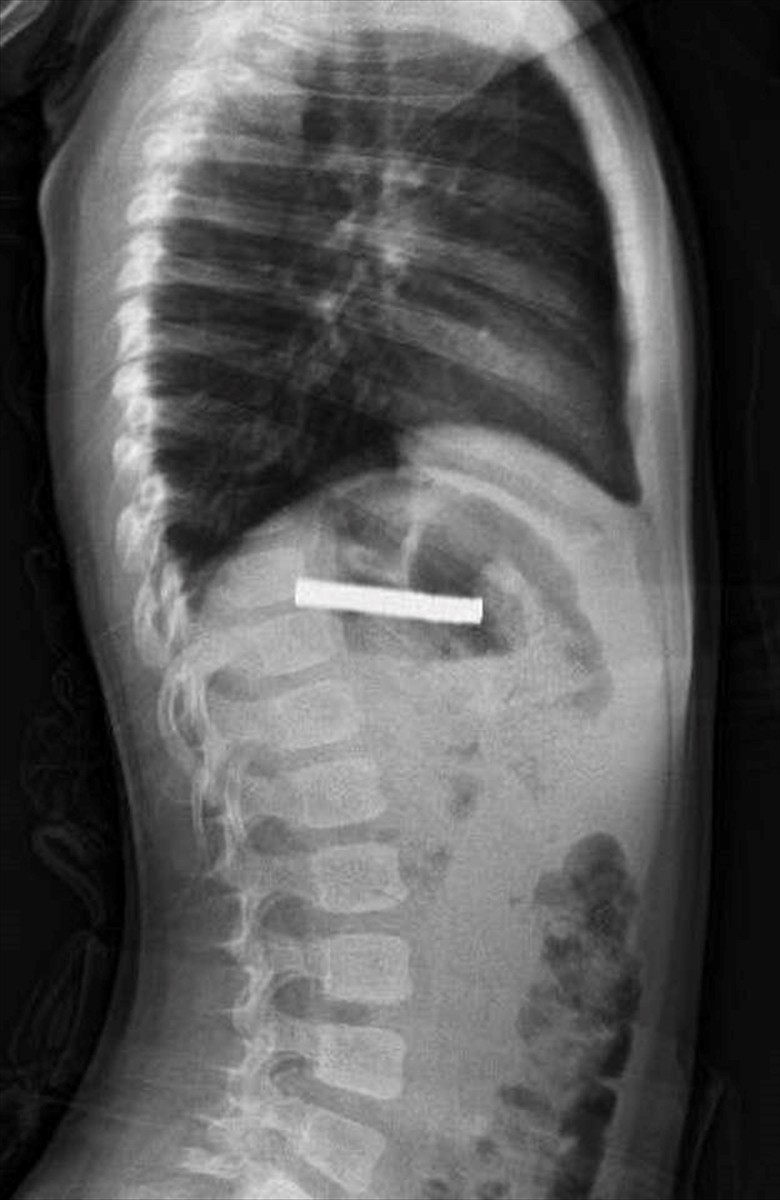

Fırat Üniversitesi Çocuk Gastroenteroloji Hepatoloji ve Beslenme Bilim Dalı Başkanı Prof. Dr. Yaşar Doğan liderliğindeki ekip, yaptığı tetkiklerde mıknatısların yemek borusunda yapışarak tıkanmaya neden olduğunu belirledi. Ekip, müdahale ederek mıknatısları başarılı bir biçimde çıkardı.

Çocuk, yapılan işlemin ardından gözlem altında tutuldu ve ailesinin isteğiyle taburcu edildi. Prof. Dr. Yaşar Doğan, "Mıknatıslar uzun süre yemek borusunda kaldığı için hasar bırakmıştı. İşlemi kolaylaştırmak için mıknatıslar mideye alındı ve mideden özel bir fileyle çıkarıldı" şeklinde bilgi verdi.